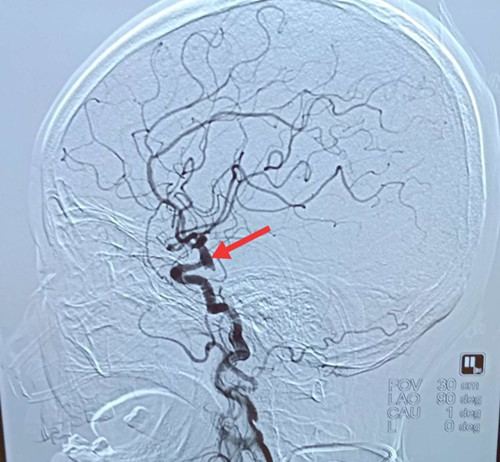

事情还得从2019年2月8日大年初四说起。刘大娘,72岁,因晨起引炉火时被呛,出现剧烈咳嗽,伴喷射状呕吐,呕吐物为胃内容物。家属立即将她送至卢龙县医院进行诊治,7点行头颅CT,结果显示蛛网膜下腔出血,可疑颅内动脉瘤破裂出血,因当地无法提供进一步诊治,家属辗转了解到秦皇岛军工医院可以进行全脑动脉造影术及相关介入治疗,于是驱车两个多小时,来到我院神经外科。医生给予紧急检查,于10点30分在介入中心行全脑动脉造影术。12点造影结束,结果显示左侧颈内动脉后交通段多形性动脉瘤。

医生立即向刘大娘家属交代造影结果及进一步介入治疗方案,经过反复沟通,家属同意为她进行动脉瘤栓塞术及颅内血管支架置放术。2019年2月9日大年初五9点40分,神经外科介入医生团队在介入中心为刘大娘实施颅内动脉瘤栓塞术及经皮穿刺脑血管腔内支架置放术。因刘大娘动脉瘤为多形性,就像“羊犄角”,这为手术增添了难度。在北京专家及陈志永医生、王振兴医生的共同努力下,经过一个多小时的精准手术,11点30分手术成功完成。